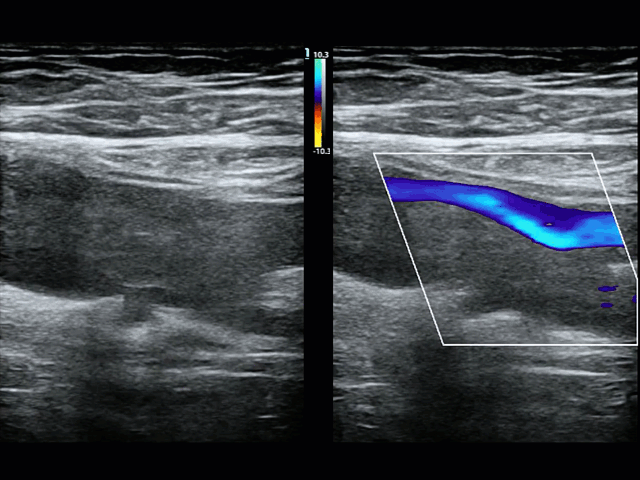

Colour Doppler: The use of colour Doppler can be a helpful adjunctive maneuver for a challenging scan. If there is slow continuous colour signal within the lumen of the vein a clot is less likley, in plane example of the this is shown in the image on the left where low velocity colour is seen occupying the lumen of the common femoral vein (vessel on the right). In the image below a side by side comparison of B-mode and colour doppler of a clot at the branch point of the femoral and deep femoral vein. In this case of clot there is absent signal within the clot and swirling turbulent flow around the edges of the clot due to the intermittent occlusion of part of the vessel wall as the clot floats back and forth in the lumen. But beware, Doppler signal is extremely dependent on being sufficiently parallel to flow, having the Nyquist limit (max/min velocities of the color scale), and gain all set appropriately so proceed with caution when using this as a rule in tool.